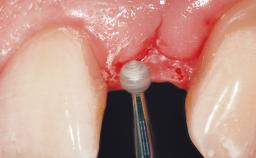

Immediate Flapless Placement of an Implant in a Maxillary Right Lateral Incisor Site

This 43-year-old male patient, a non-smoker, came to our practice because of a fracture of tooth 12 caused by a bicycle accident. Due to the combined para- and infrabony crown and root fracture, tooth extraction, and subsequent implant placement were suggested to the patient as the therapy of choice. The patient had high esthetic expectations with regard to the treatment outcome and asked for an immediate fixed provisional restoration. His individual esthetic risk profile summed up to a medium esthetic risk.